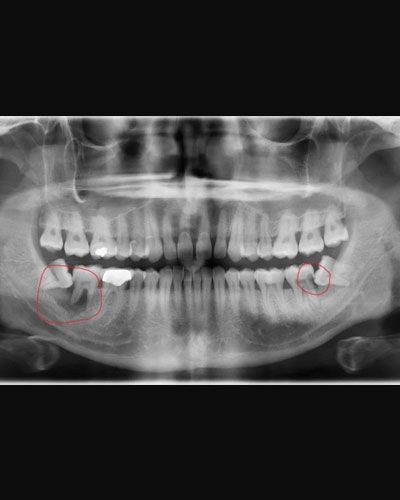

HÌNH ẢNH THỰC TẾ TRƯỚC - SAU ĐIỀU TRỊ NHỔ RĂNG KHÔN

Khách hàng Nguyễn Chí Tài